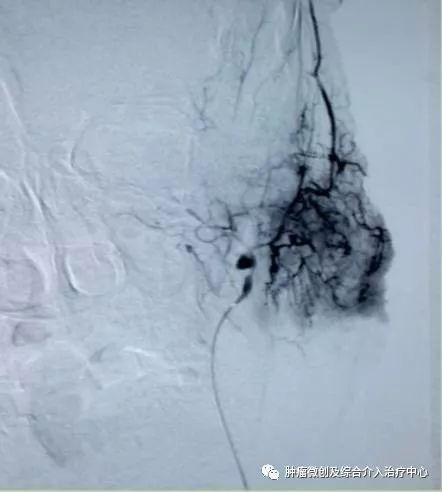

(鼻咽癌颈部转移瘤破溃出血,DSA造影提示左颈部病变血管迂曲、紊乱,内有出血)

运城第一医院肿瘤介入科专家,运城市第一医院介入科专家